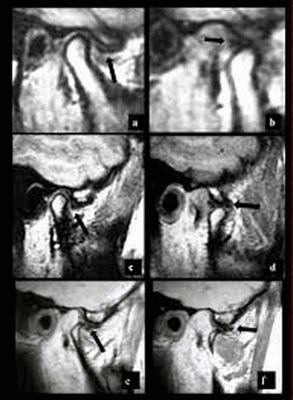

МР-изображение ВНЧС. a, c, e - в открытом положении, b, d, f - в закрытом. Стрелками показано переднее смещение диска с редукцией (a,b,c,d), без редукции (e,f). Выявлен остеофит на мыщелке (e,f).

Однозначно ответить, какое из исследований лучше, нельзя. Методы могут дополнять друг друга. КТ нижней челюсти визуализирует костные структуры лицевого отдела черепа, в то время как МРТ используют для оценки мягких тканей. В обоих случаях получают послойные изображения изучаемой области, компьютер при необходимости преобразует их в 3D-модель.

При поражении ВНЧС делаютя МРТ с функциональными пробами в следующих положениях: с закрытым ртом, приоткрытым и полностью открытым. Такой подход позволяет визуализировать весь процесс движения в различных проекциях. Используя полученные результаты, врач поймет, в какой момент происходит сбой.

В норме кости не соприкасаются, но патологическая подвижность диска приводит к трению и болезненным ощущениям. Последний может изменять положение в различных направлениях, наиболее распространено переднее смещение.

Примером еще одной патологии, которую помогают установить функциональные пробы, является фиксированный, перемежающийся вывих и подвывих. Специалист увидит на изображении с закрытым ртом смещение внутрисуставного образования, а в открытом состоянии оно вернется на место. Описанный результат будет свидетельствовать о перемежающемся вывихе челюстного сочленения.